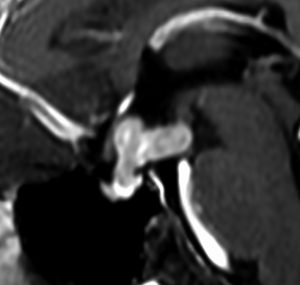

ICE化学療法投与開始から数日で小さくなります

この例は古いので第3脳室開窓術 ETV をしていません。左はICE化学療法前。中央は9日後。右は25日後です。閉塞性水頭症があっても1週間くらいで中脳水道が通って水頭症は改善します。ジャーミノーマであれば,ICE化学療法1コースでかなり縮小するはずです。このような顕著な効果がない時には,逆にジャーミノーマ以外の胚細胞腫瘍が混在していると考えた方がいいでしょう。多くは奇形腫の混在です。